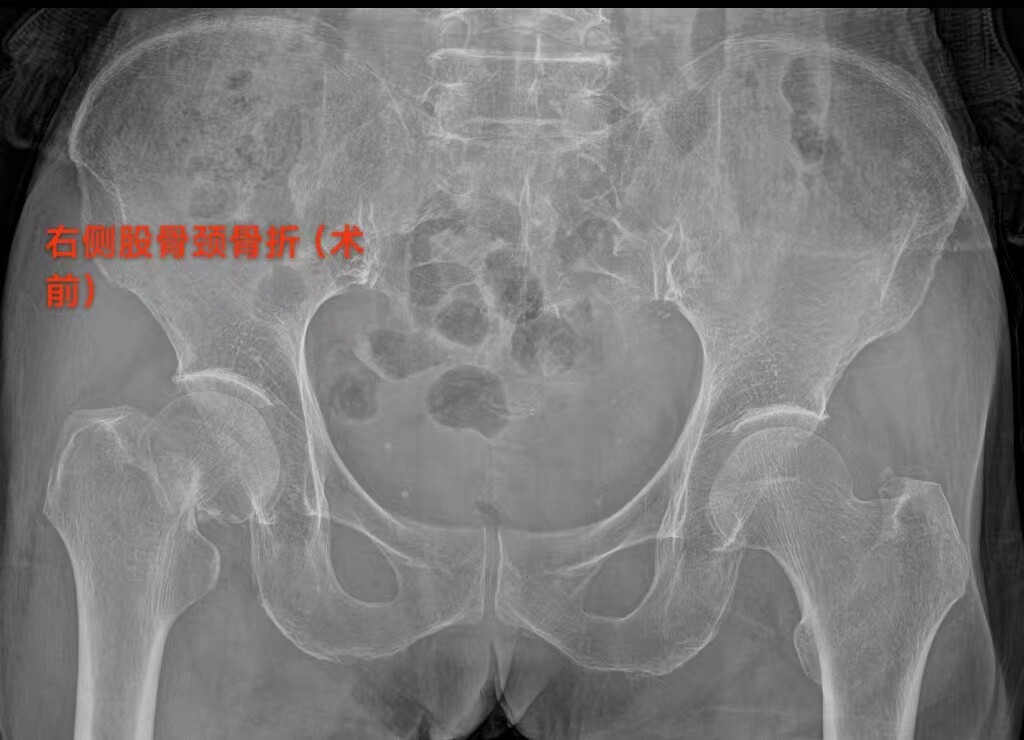

81 岁患者的朱奶奶,因摔伤致右髋部疼痛 2 天入院,确诊为右侧股骨颈骨折。永兴县人民医院骨二科团队在充分评估朱奶奶的病情后,决定采用 “保留梨状肌人工股骨头置换术”,术后第一天,朱奶奶便在医护人员的保护下顺利下地站立并行走,疼痛感明显减轻,关节活动功能恢复良好。